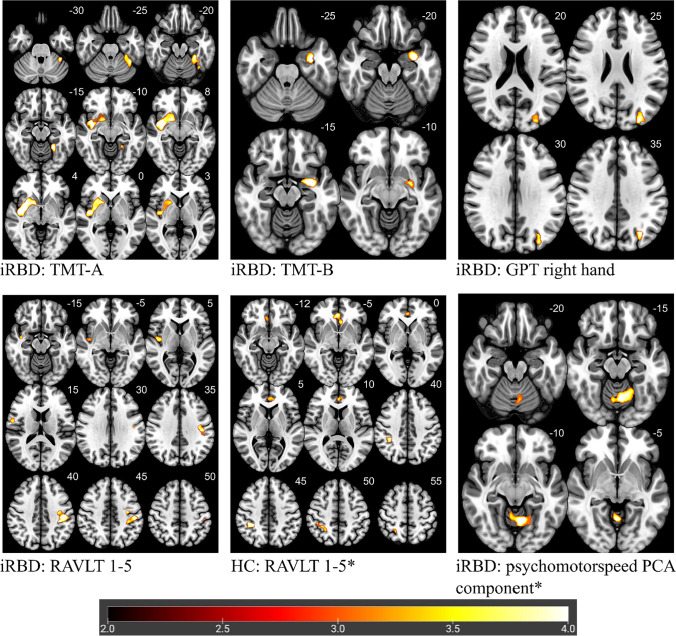

Using VBM, the performance in TMT-A, TMT-B, GPT right hand, RAVLT 1–5 and the PCA component psychomotor speed were identified to significantly correlate with brain morphology in iRBD patients (Fig. 2; Supplemental Table 4).

Fig. 2.

Correlation between performance in cognitive tests and brain morphology analyzed with VBM. Note. Highlighted significant clusters thresholded at p < 0.05 at cluster level, corrected for family wise error. Color scale represents decimal logarithm of p-level. Z-coordinates in the Montreal Neurologic Institute space (in millimeters) are indicated next to each slice (top right). Lower values of Psychomotor speed (PCA component) indicate better cognitive performance. HC = healthy controls; iRBD = isolated rapid eye movement sleep behavior disorder; TMT-A = Trail Making Test, part A; TMT-B = Trail Making Test, part B; GPT = Grooved Pegboard Test; RAVLT 1-5 = Rey Auditory Verbal Learning Test 1-5, PCA = principal components analysis. * indicating negative correlation

TMT-A performance correlated positively with a cluster in the right hemisphere including regions of the putamen, insula and temporal superior lobe (p < 0.001) and a second cluster in the left cerebellar hemisphere (p = 0.026). TMT-B performance correlated positively with clusters in the left hemisphere including the amygdala, hippocampus and parahippocampal gyrus (p = 0.050). Right-hand GPT correlated positively with a cluster containing regions in the occipital and parietal lobe of the left hemisphere (p = 0.043). A cluster containing parts of the precentral, postcentral and supramarginal gyrus of the left hemisphere (p = 0.038) as well as another cluster in the right hemisphere containing parts of the insula, hippocampus and temporal lobe correlated positively with RAVLT 1–5 (p = 0.023). The PCA component psychomotor speed showed a significant negative correlation with regions in the rostral vermis and adjacent parts of both cerebellar hemispheres (p = 0.010).

In HC no correlations between brain morphology and the results of TMT-A, TMT-B, GPT right hand and psychomotor speed were detectable. Correlation analysis for RAVLT 1–5 in HC showed one significant cluster, which was located in different brain regions and had a different direction (negative) than correlations in iRBD patients. The cluster is in the cingulum and frontal lobe of both hemispheres (p = 0.020).